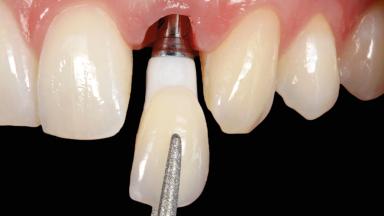

Immediate Implant Placement and Immediate Provisionalization with a Prefabricated-Shell Provisional Crown

In this case, Arndt Happe describes how he achieved a stable outcome at 5 years by giving careful attention to the coronal aspect of the transmucosal area of the provisional, creating a slim emergence profile.

A healthy 31-year-old female patient presented with a failing maxillary left lateral incisor crown. The crown regularly loosened, and the remaining tooth was neither restorable nor rational to treat. The patient had a high smile line, a medium soft tissue biotype with a compromised mesial papilla (shorter than the contralateral one), and a horizontal scar in the buccal soft tissue as a result of past periapical surgery.